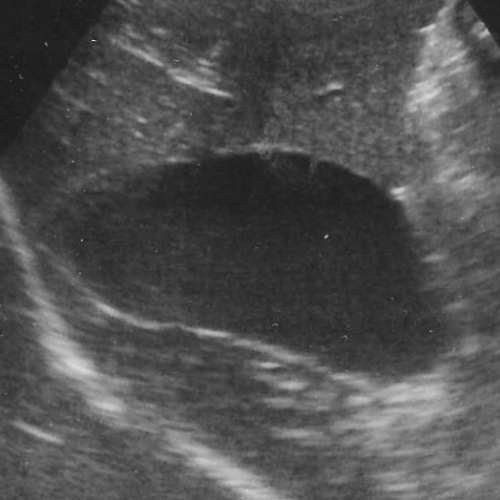

左下の写真が胆嚢粘液嚢腫の胆嚢の超音波検査のイメージです。本来は、画像上で真っ黒く抜けている円形の胆嚢の断面像に「キウイフルーツ」の切り口のように見えるようなパターンを生じるのが典型的ですが、その他に胆泥症との区別が難しいものなど、幾つかのバリエーションに富む異常を呈します。比較のために正常な胆嚢を右の写真を右写真に示します。

下の超音波像は胆嚢破裂の初期の胆嚢をみたものです。中央部に胆嚢粘液嚢腫がみられますが、黄色腺の間に示されている「三角形の黒いエリア」が胆嚢壁の外側に広がっています。これは胆嚢壁の裂け目から内部の「粘液状物」が腹腔内に出ていたり、周囲の組織との強い癒着や炎症を示す画像です。ご参考までに右が正常の胆嚢です。

上記の患者さんは食欲がなく、頻発する嘔吐と腹部痛を理由に来院いたしました。その後直ちに胆嚢摘出術を実施して事なきを得ています。